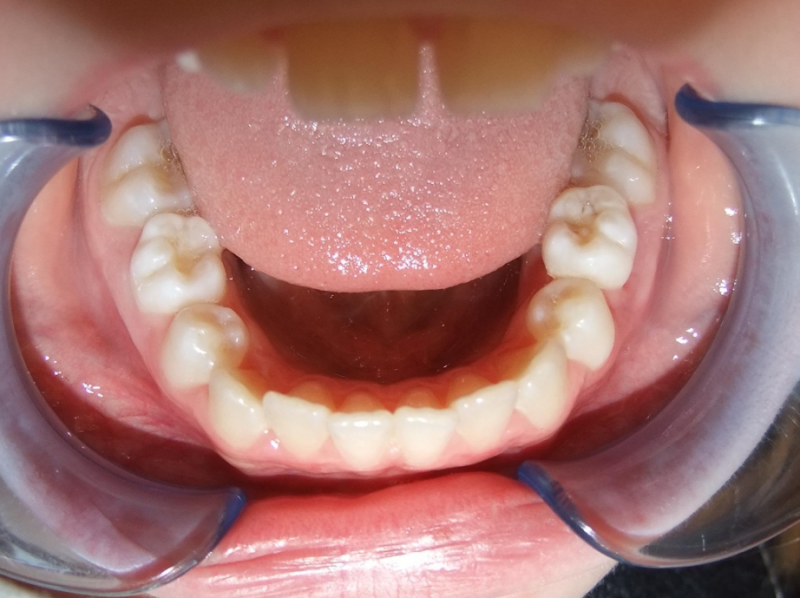

eindfoto

Beschrijving

Leeftijd bij aanvang: 9 jaar

1-6 Bonded Hyrax + volledig vast onderkaak & TransForce

7-13 Twin Block

14-26 volledig vast boven- en onderkaak + TPA

Leeftijd bij retentie: 11 jaar